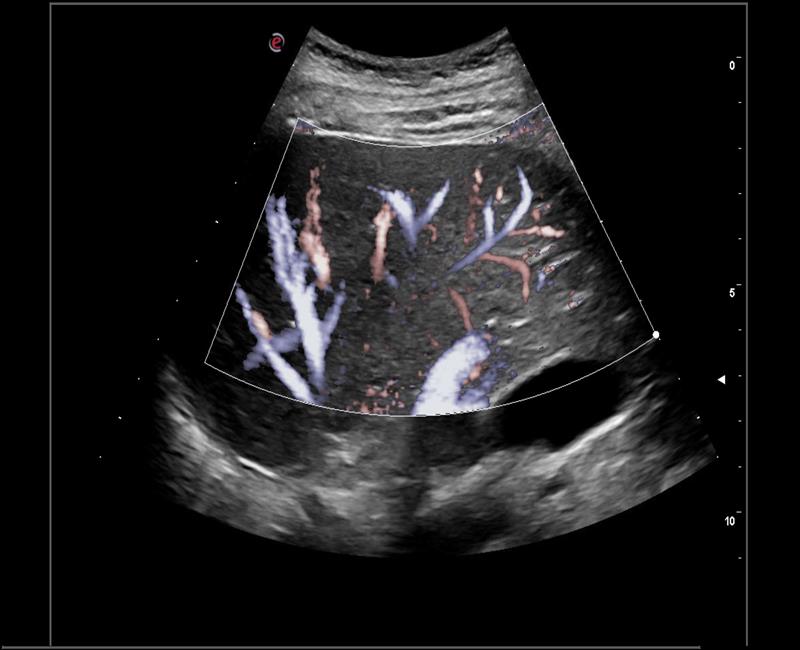

XFlow – Tăng cường độ nhạy trong siêu âm mạch máu, đặc biệt là các mạch máu nhỏ, có vận tốc thấp.

may sieu am mylab x6